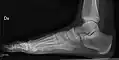

• Ankle - AP/Mortice and Lateral

• Calcaneum - Axial and Lateral

• Foot / Toes - Dorsoplantar, Oblique and Lateral.[19]